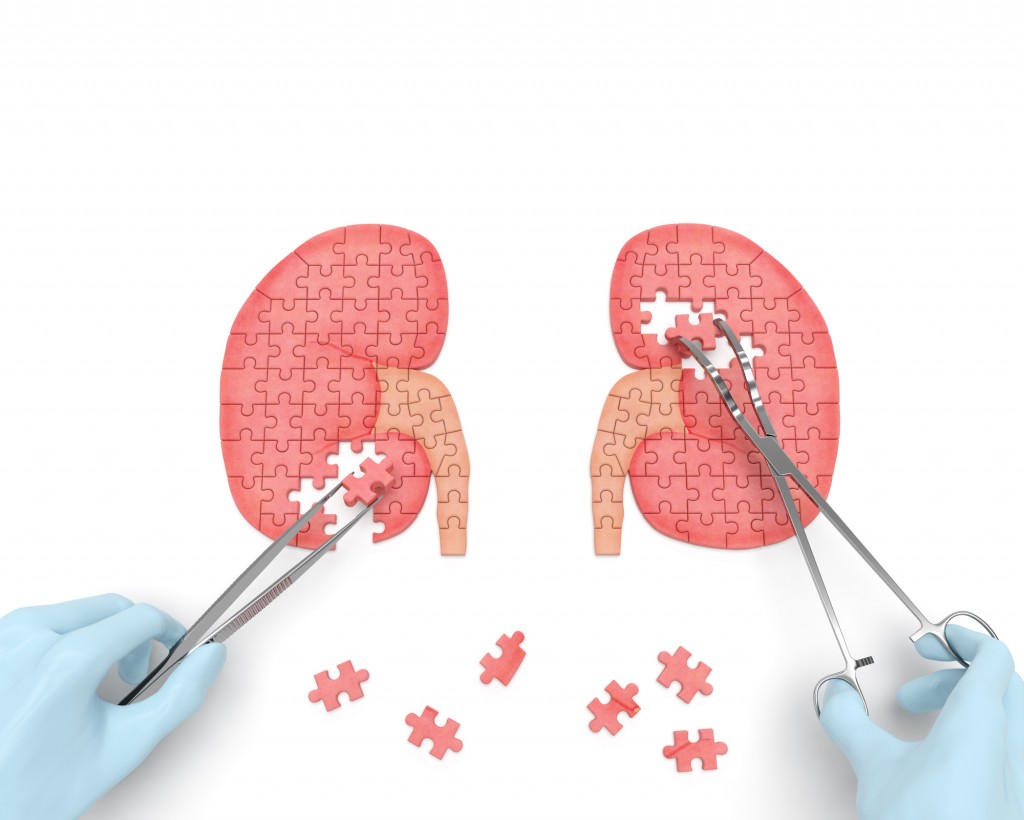

Quiste renal: Qué es y cuáles son sus síntomas

Los quistes renales son bolsas redondas de líquido que se forman en los riñones o sobre estos. Los quistes renales pueden estar asociados con trastornos graves que pueden afectar la función renal. Sin embargo, con mayor frecuencia, los quistes renales son un tipo llamado «quistes renales simples», es decir, quistes no cancerosos que rara vez causan complicaciones.

Los quistes renales simples a menudo se detectan durante una prueba de diagnóstico por imágenes que se realiza por otras enfermedades. Por lo general, los quistes renales simples que no causan signos ni síntomas no requieren tratamiento.

Estos pueden clasificarse en cinco tipos: I, II, IIF, III y IV (clasificación de Bosniak). Los tres primeros solo requieren controles radiológicos periódicos y son los que se ven habitualmente. Los tipos III y IV obligan a intervención quirúrgica, bien exploradora o bien para la extirpación del quiste. En ocasiones, los tipos IIF y III pueden confundirse, por lo que requieren de mayor seguimiento o de la realización de más pruebas radiológicas hasta llegar a un diagnóstico de certeza.